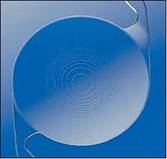

3. IOL & related consumables There are multiple IOL choices available for the surgery which are explained below. These lenses can be inserted through a small 1.8 to 2.8 mm opening

Aberration free/ Aspheric IOLS

These IOLs gives good quality of vision post operative due to the lens design, it also improves the contrast sensitivity of the patient

and good night vision. These lenses also filter the harmful UV light and blue light which are said to be harmful to the retina.

Multifocal IOLs [Bifocal and Trifocal]

These IOLs provide clear vision for all distances hence almost 90% of the day-to-day activities can be performed without the need for additional glasses. Rarely the patient may experience glare during nights post operatively but usually gets adapted within a few months.

Accomodating IOLs These IOLs have flexible hinges that enables them to change focus for different distances hence providing clear distance, intermediate and near vision without glasses.

Hydrophilic Acrylic Lenses for Cataract Surgery

Hydrophobic Lenses for Cataract Surgery